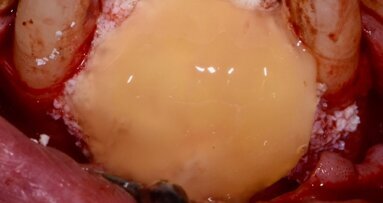

All’esame clinico presenta i quattro incisivi superiori malposizionati, con diastema per evidenti problemi parodontali. Perdita importante di supporto parodontale, presenza di tasche superiori a 6 mm, mobilità di tipo 2/3 su tutti i quattro elementi (Figg. 1-4).

Il piano di trattamento prevede l’estrazione degli elementi dentali, l’inserimento di due impianti e la realizzazione di una protesi fissa di quattro elementi. Il problema da gestire è quello della fase provvisoria. Non è ipotizzabile una protesi mobile e quindi programmiamo di inserire subito dopo l’intervento un provvisorio immediato. Questo ci consente di condizionare da subito i tessuti periimplantari e anche le zone dei ponti. Si rileva un’impronta digitale (Figg. 5, 6), e la programmazione degli impianti viene effettuata con un software di chirurgia guidata (Fig. 7) e la posizione degli impianti nello spazio biologico e nello spazio protesico viene fatta sulla base di una ceratura diagnostica (Figg. 8, 9). Inseriamo gli impianti virtuali nell’osso disponibile (Figg. 10-13) e in relazione all’aspetto protesico correggiamo l’asse di inclinazione degli impianti con componenti secondarie angolate a 17° (Figg. 14, 15). Questo ci consentirà di realizzare una protesi avvitata con i fori situati nella zona palatale.

Il nostro obiettivo è quello di riuscire a dare alla paziente un provvisorio immediato nell’arco di due ore. Questo diventa possibile perché abbiamo utilizzato un flusso digitale fin dall’inizio. In laboratorio vengono realizzate la dima chirurgica (Figg. 16, 17), la dima protesica (Fig. 18) e anche il provvisorio (Figg. 19-21) che contiene delle alette di riposizionamento. Il tutto gestito con modelli digitali sui quali saremo in grado di funzionalizzare il provvisorio post-chirurgico (tecnica DIL). In un caso come questo se utilizziamo un flusso digitale possiamo evitare subito dopo la chirurgia di rilevare un’impronta degli impianti inseriti. Infatti, utilizziamo una dima chirurgica che ci faciliterà le fasi di intervento. La dima ci consentirà di non fare lembi e nessuna incisione di rilascio (Fig. 22), dopo aver inserito gli impianti (BLX Straumann) (Figg. 23-31) e aver controllato il loro alloggiamento, inseriamo sugli stessi dei transfert da impronta (Fig. 32).

Alloggiamo la dima protesica (Fig. 33), e blocchiamo i transfert con della resina trasparente (tecnica DIL) (Figg. 34, 35). In questo modo possiamo far riposare il paziente in studio dopo appena 35 minuti dall’inizio dell’intervento. La dima protesica, infatti (Fig. 36) con i transfert inseriti viene completata con l’unione degli analoghi ai transfert (Fig. 37). L’insieme così composto viene riadattato sul modello master digitale iniziale (Figg. 38-40) sul quale era stata costruita sia la dima chirurgica che la dima protesica come anche il provvisorio. Gli analoghi vengono bloccati sul modello con resina trasparente (Figg. 41-43). Alloggiamo il provvisorio sul modello master digitale così ottenuto (Figg. 44, 45).